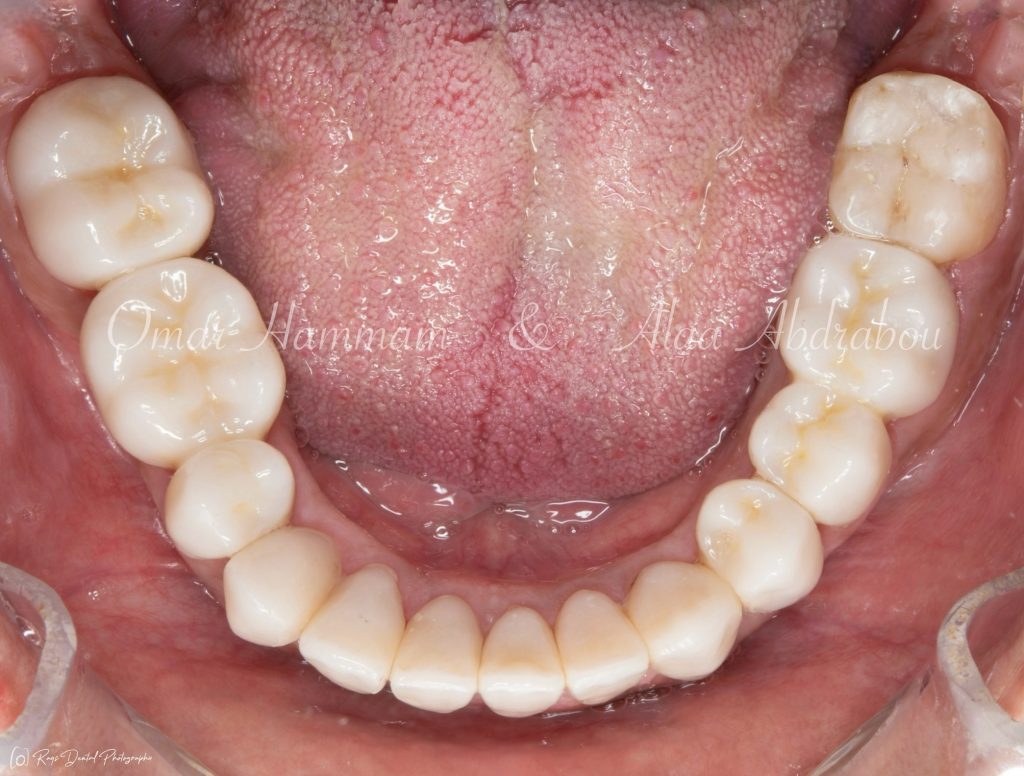

Immediate occlusal scheme after cementation (before any adjustments):

Showing “Occlusal equilibration”, where Stable occlusion is achieved , in which there are Stable contacts of equal intensities on all teeth in centric occlusion showing Group Function occlusion.

Occlusal forces are distributed on more occlusal contacts, Acting as a group to distribute occlusal forces, thereby increasing efficiency of mastication and performing lateral movements atraumatically.